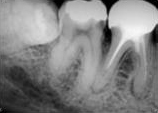

antes depois